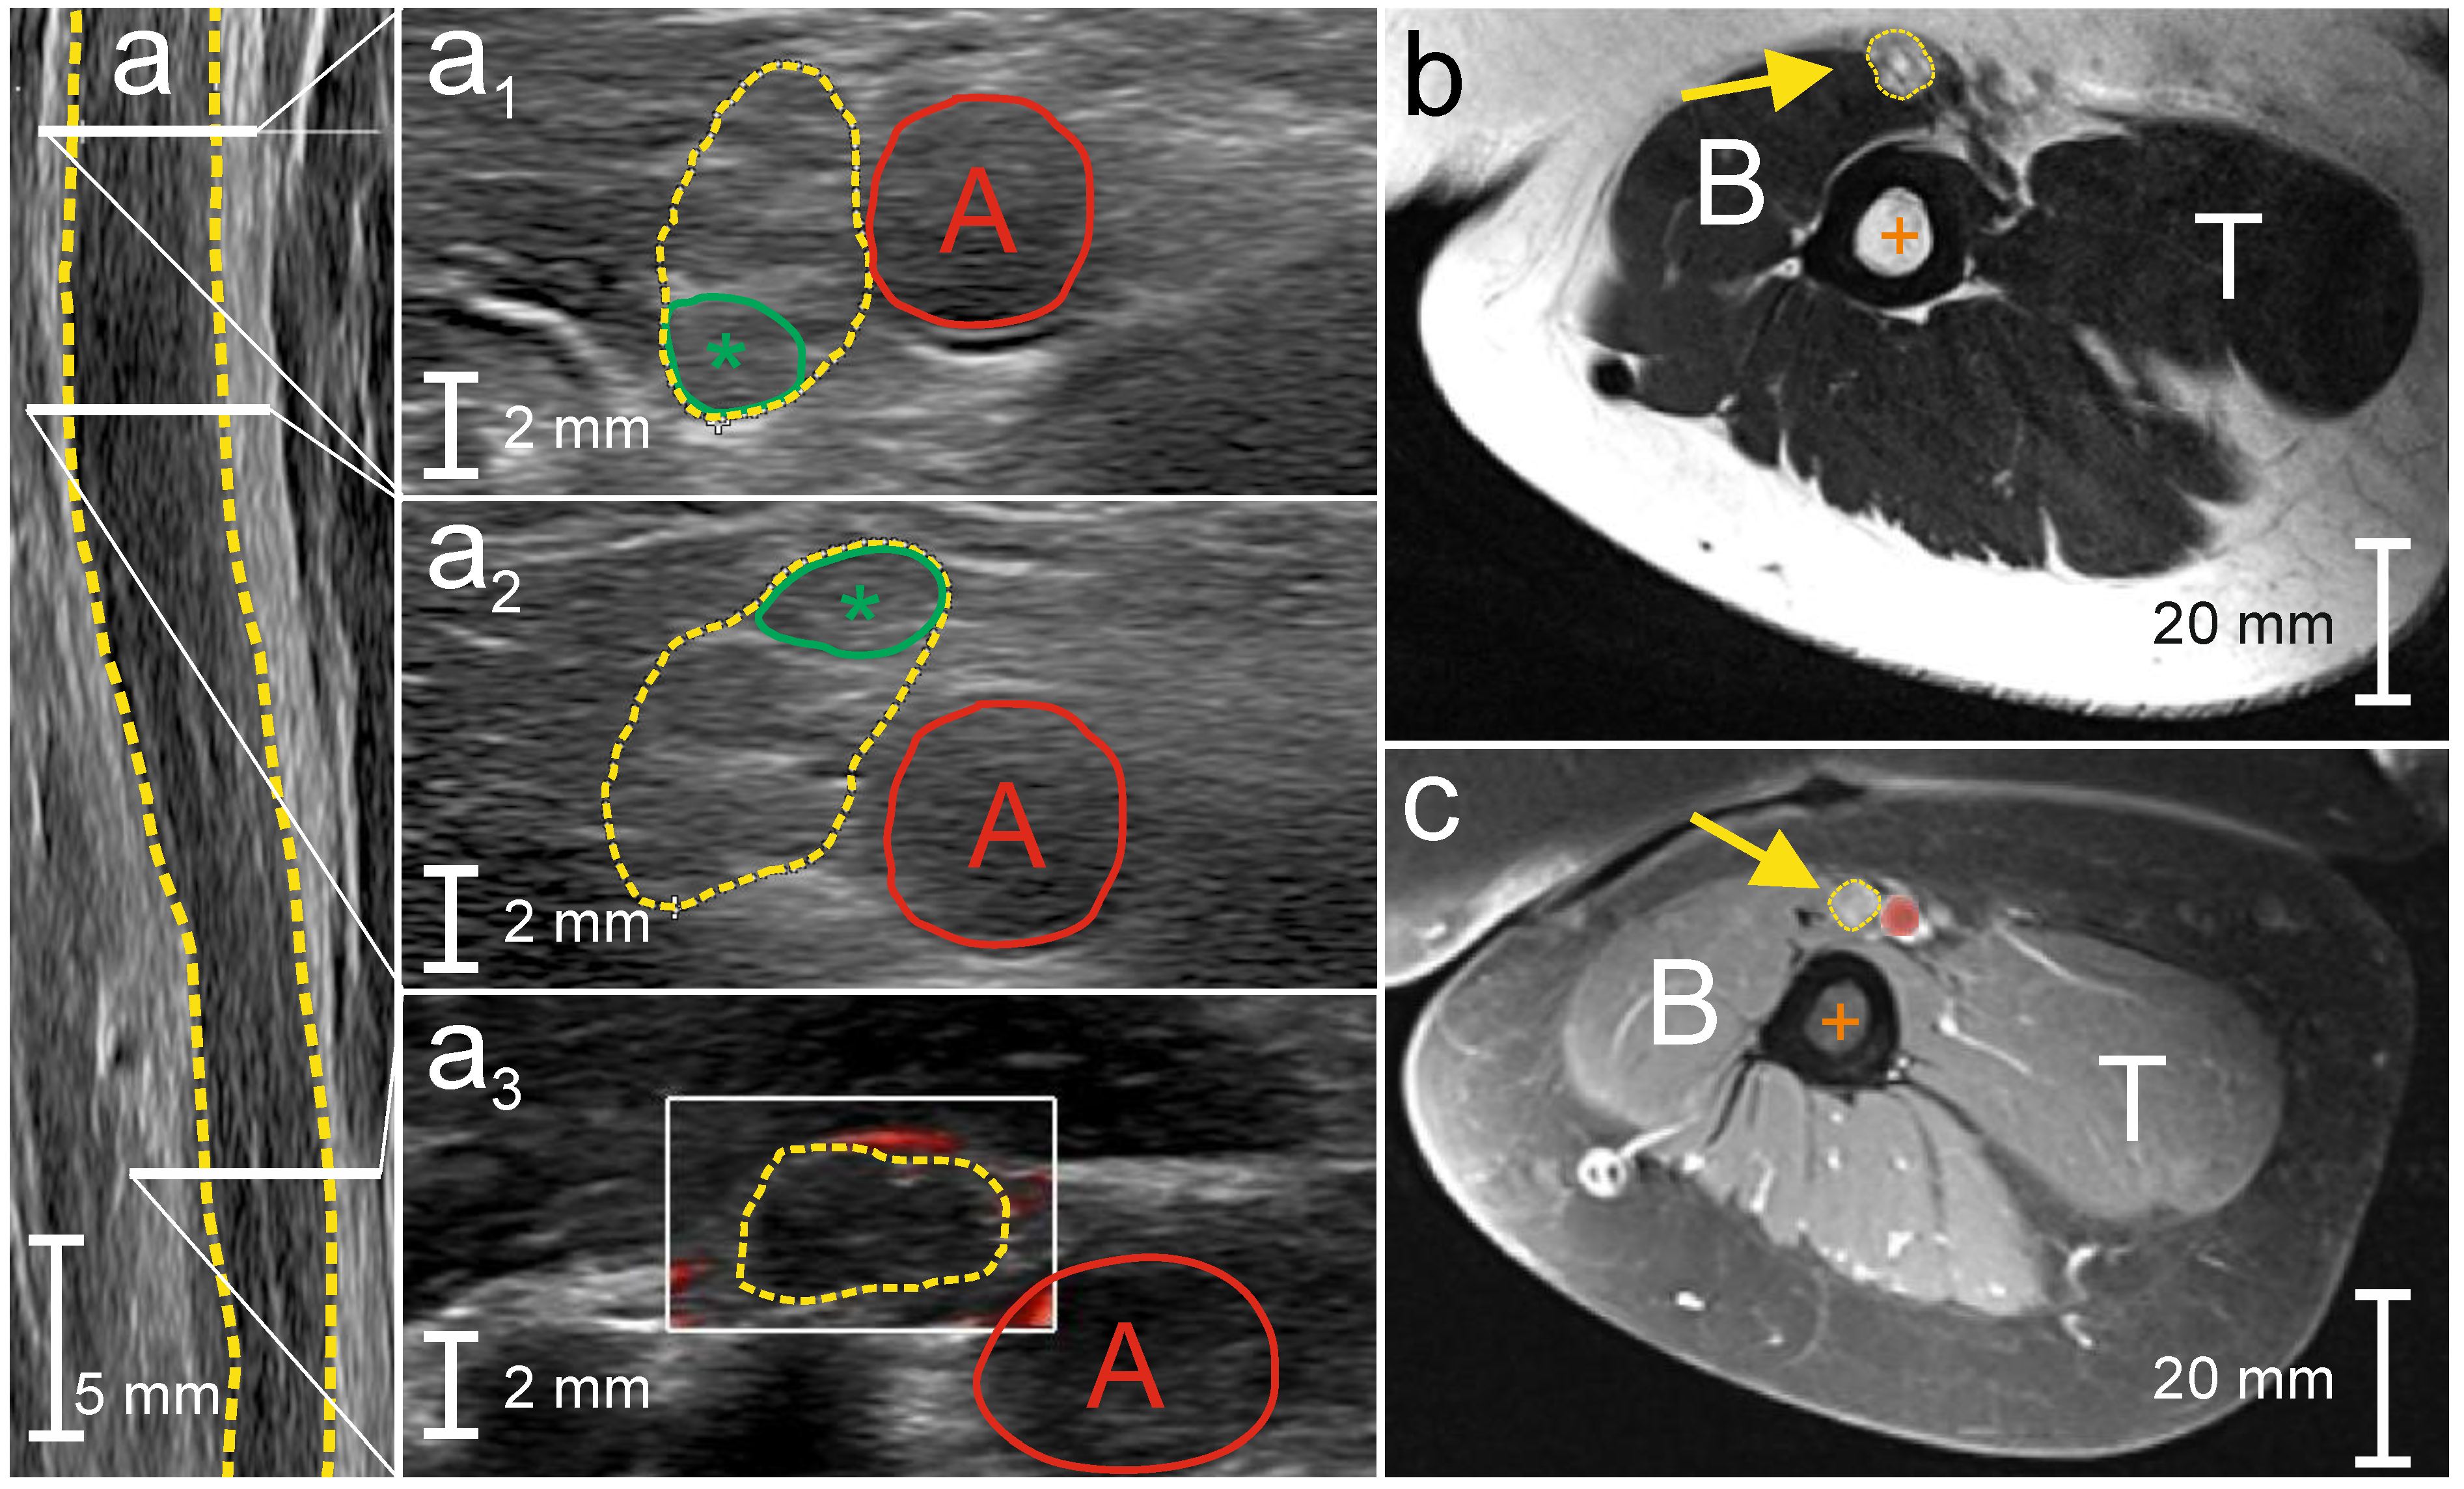

- Schreiber, S.; Schreiber, F.; Peter, A.; Isler, E.; Dörner, M.; Heinze, H.-J.; Petri, S.; Tempelmann, C.; Nestor, P.J.; Grimm, A.; et al. 7T MR neurography-ultrasound fusion for peripheral nerve imaging. Muscle Nerve 2020, 4, 521–526. [Google Scholar] [CrossRef]